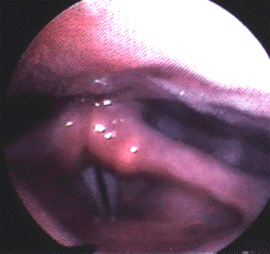

The photo below on the left shows the larynx during speech in a woman with laryngeal MTD. You cannot actually see the true vocal folds in this picture since the false vocal folds are inappropriately closing and they block the view of the true vocal folds lower down. Her voice was both hoarse and strained.

The photo on the right is taken while the same patient is being coached by a speech pathologist. Note that the appearance of the vocal folds is dramatically different. Instead of being pinched together, the false vocal folds are appropriately separated. The true vocal folds can actually be seen and they are much less tense. Stroboscopic exam shows very little movement in the left photo, but nice vibration when the patient is being coached by the speech pathologist in the right photo.

Close up of MTD in woman's vocal cords

Close up of MTD in woman's vocal cords while being coached